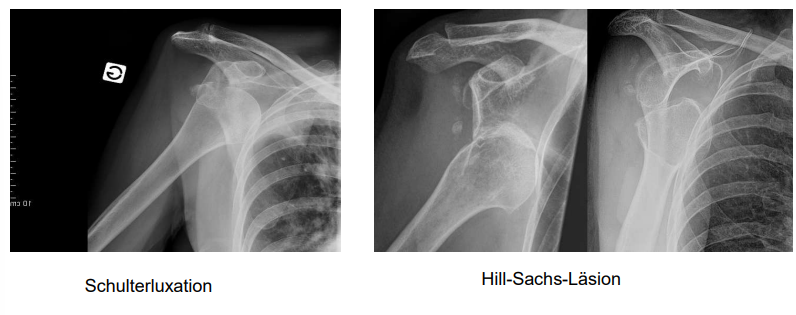

Schulterluxation

Abschlagen, Eindellen des Knochen → Hill-Sachs-Läsion

Schultergelenkluxation

a) Nach unten

b) Nach vorn

c) Nach hinten

d) Sonderform

c & d sind selten